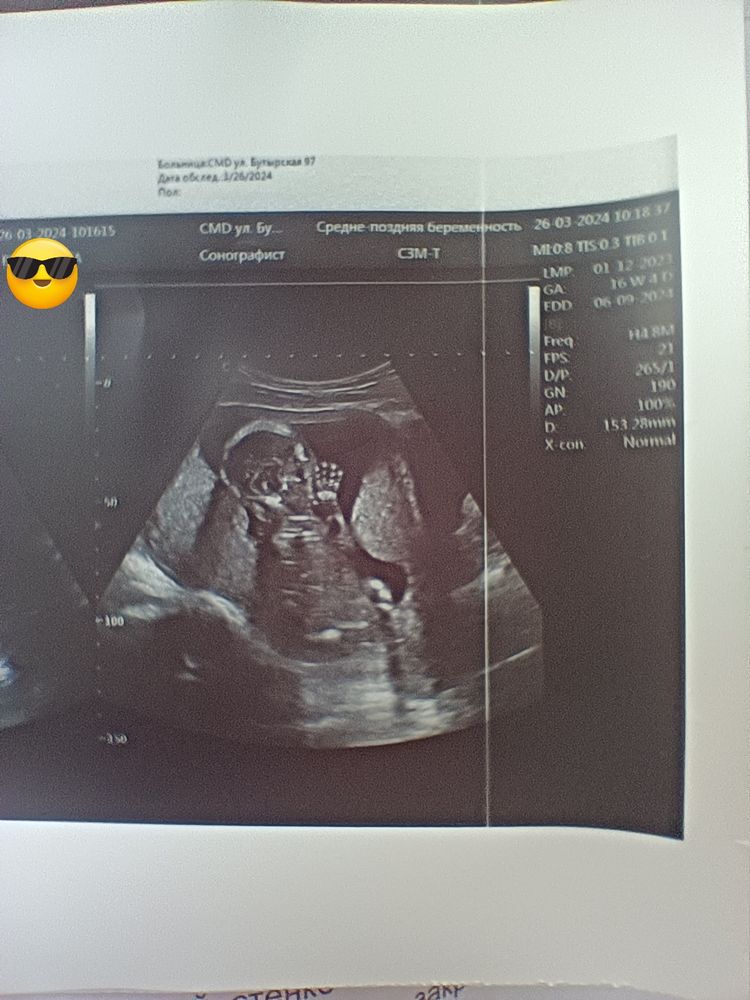

УЗИ, КТГ, доплерСегодня повидались с малышом 🥰🥰. Все у нас хорошо..в девочку не превратился 😂😂 164 гр весим уже. Сидим на попе, немного пуповиной обмотался но не туго.по всем параметрам на 16 недель мы.

Сегодня повидались с малышом 🥰🥰. Все у нас хорошо..в девочку не превратился 😂😂 164 гр весим уже. Сидим на попе, немного пуповиной обмотался но не туго.по всем параметрам на 16 недель мы.